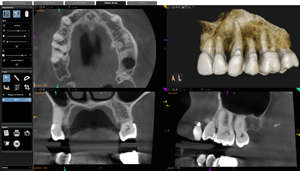

3D Imaging / CBCT

(Cone Beam Computed Tomography)

Technology has progressed to the point where it is possible to make 3D images or pictures of teeth and the surrounding structures. The Carestream 8100 Computed Tomography unit allows for root canal specific images to be made that allow us to determine the exact shape of your tooth. This technology helps us in preventing problems from arising in cases where the current 2D images aren’t clear, situations of calcified teeth or unusual tooth anatomy or pathology. This is also very helpful when we are evaluating teeth for retreatment because it allows us to see all the way around a tooth’s roots and uncover signs of fracture that might not be present on 2D imaging. It’s painless, no sensors are put in your mouth, and it only takes about 7 seconds to take a picture.